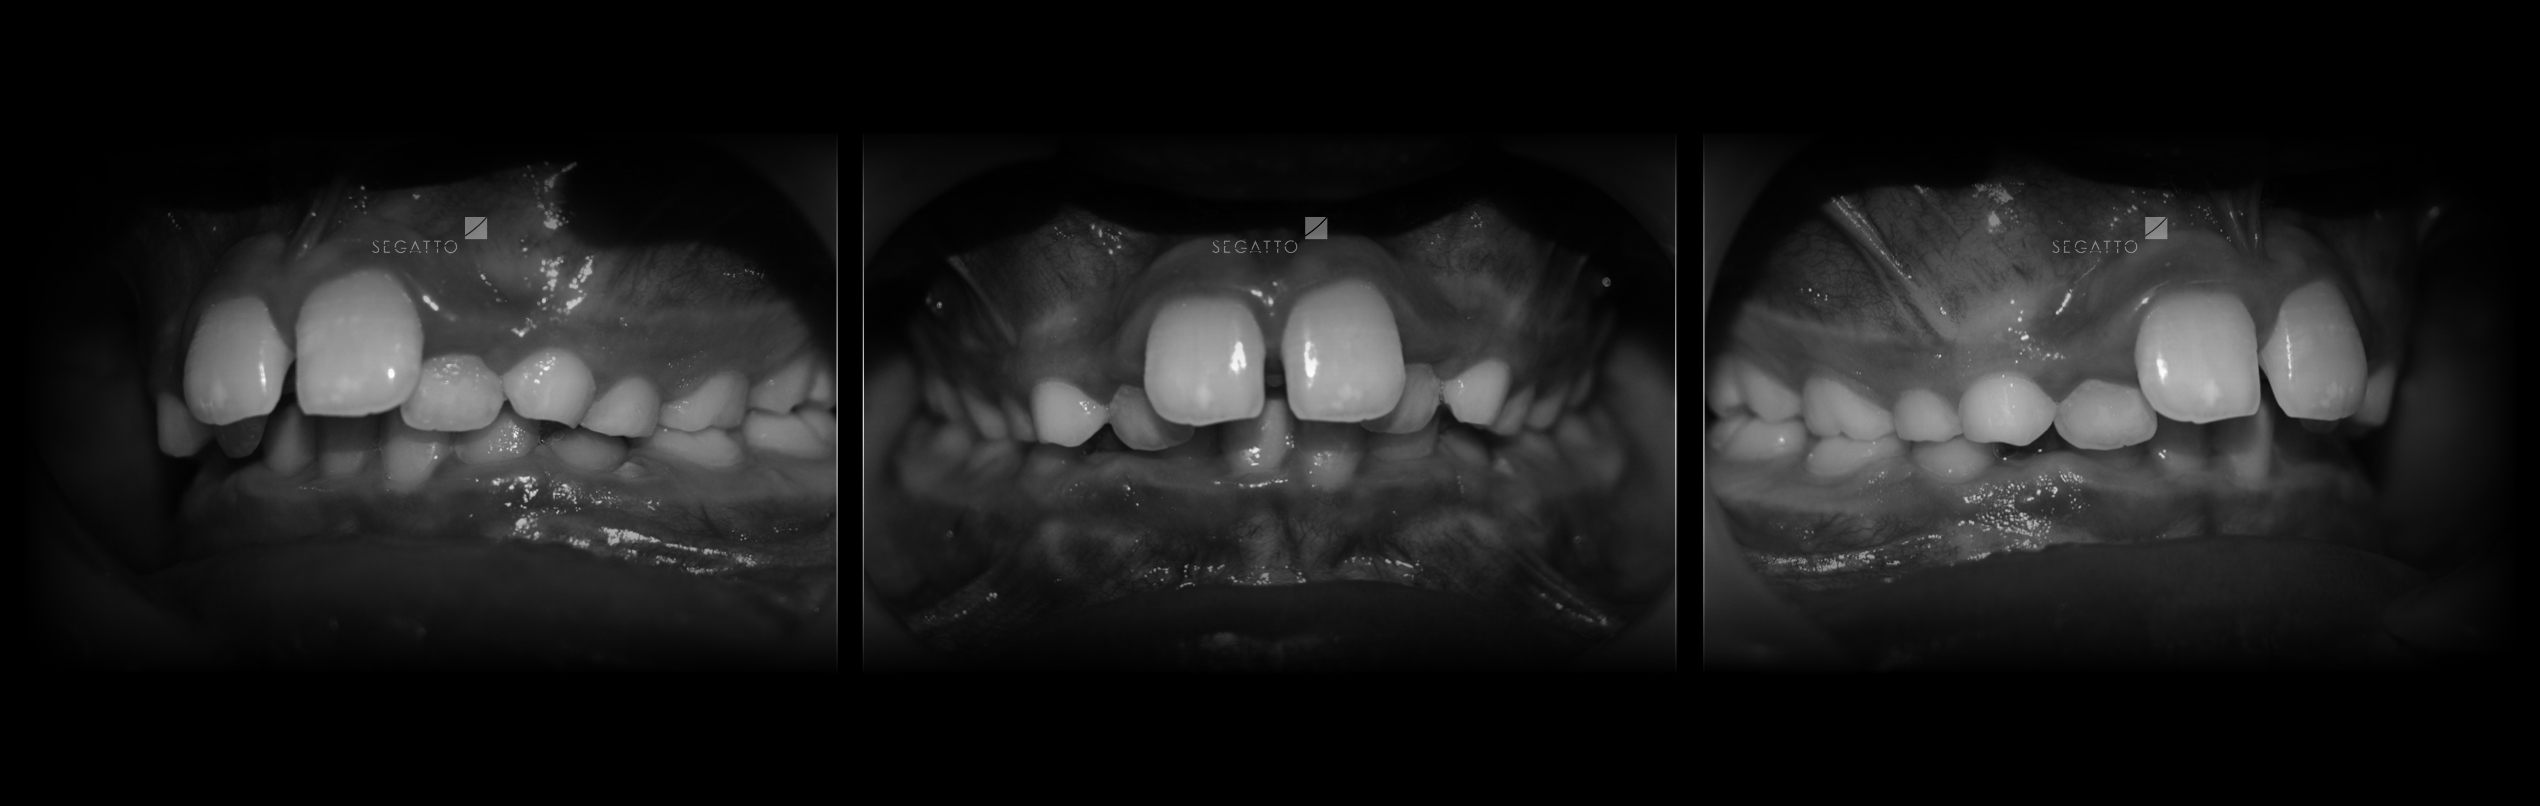

Orthodontics

Cases